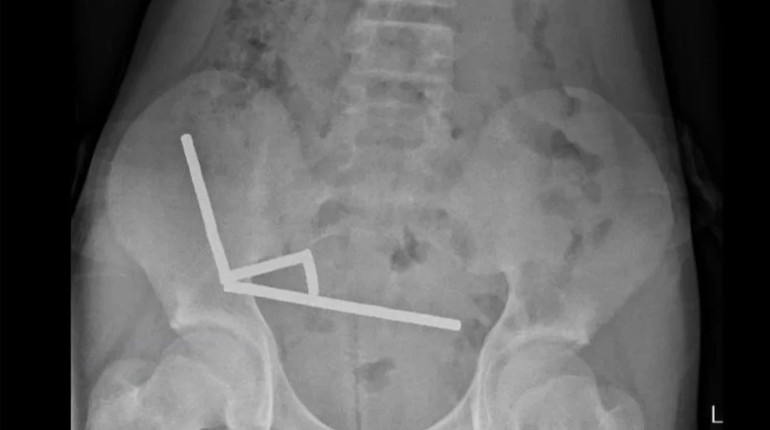

An X-ray showed that inside the child’s intestines foreign objects were lined up in four straight lines.

“They were in separate parts of the intestine, held together by magnetic force”the doctors added.

The pressure of the metal caused necrosis (death of tissue) in four areas of the small intestine and cecum. To save the child, doctors performed an operation that removed dead tissue and pulled out the magnets.